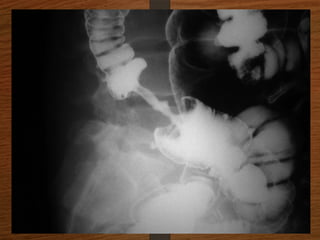

Doubt about the

diagnosis on the plain

radiographs

Contrast enema

• Features seen at the point of torsion include a

smooth, curved tapering of the colonic lumen, like a

hooked beak (the bird of prey sign)

• the mucosal folds often show a ‘screw’ pattern at the

point of twist

Doubt about the diagnosison the plain radiographs Contrast enema

• 33.

Contrast enema • Featuresseen at the point of torsion include a smooth, curved tapering of the colonic lumen, like a hooked beak (the bird of prey sign) • the mucosal folds often show a ‘screw’ pattern at the point of twist